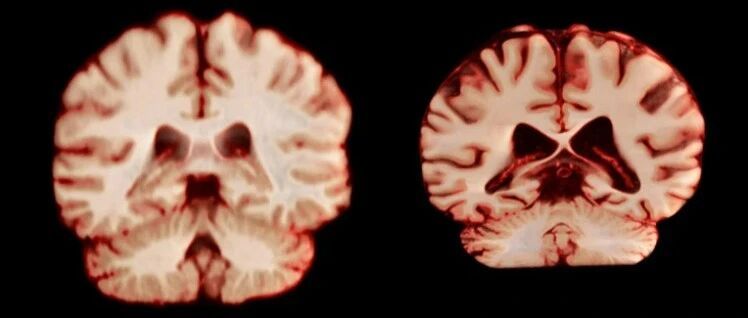

阿尔茨海默病为何“偏爱”女性?

这里是上海市科学技术协会的上观号。让我们一起来分享科学信息,享受科学生活,主张科学态度,共建科技工作者之家。